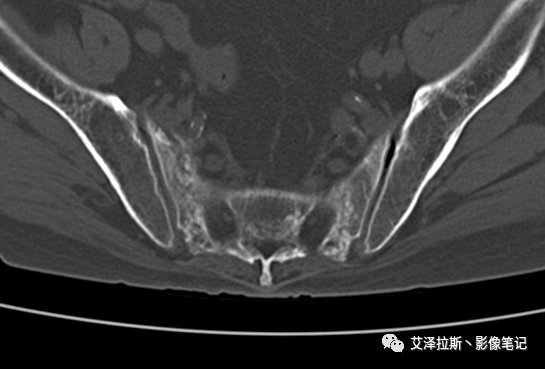

病例1:患者,女性,88岁,重度骨质疏松。

CT平扫:

X线、CT:骶骨重度骨质疏松,双侧骶骨翼皮质断裂,分别见迂曲走行的纵行透亮线位于骶孔外侧,大致与骶髂关节间隙平行,骨折端局部可见骨痂、骨质硬化。

骶骨功能不全骨折

①单侧或者双侧骶骨翼骨折,典型者呈“H”形,即“Honda征”;

②骨折线位于骶孔外侧(如下图,主要发生于1区),通常可能会伴随耻骨的功能不全骨折(如:病例2 右侧耻骨上支骨折,L5双侧横突骨折);

③愈合期骨折线模糊,骨痂形成,骨质硬化;